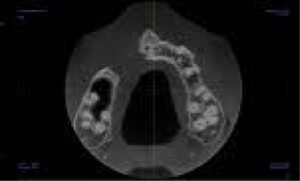

There is a large unilocular moderately well-defined radiolucency, 23 x 15 x 14 mm extending from the UR5 apex to the midline but not invading the nasopalatine canal. There is a “through and through” destruction of the buccal and palatal cortical bony plates, as well as destruction of the alveolar bone ridge. The right maxillary sinus and floor of the nose are not involved. There is external root resorption of the UR4.

The lack of bone expansion, resorption of UR4 roots plus the “floating tooth” appearance of UR4 all suggest the possibility of malignancy. In a case such as this an urgent referral to an oral surgeon is recommended for biopsy to determine the diagnosis and rule out a malignancy.